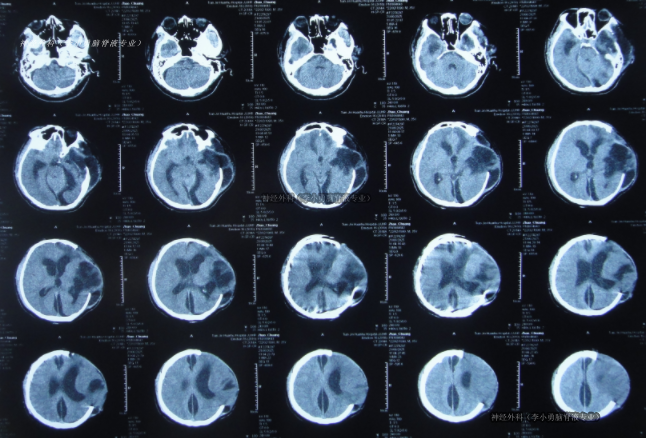

開顱術后第4天放置腦室外引流,第7天因擔心感染拔除。患者雖逐漸清醒,但術后第29天轉至第3家康復醫(yī)院后,出現(xiàn)嘔吐、問話不答、右側肢體癱瘓。復查CT示腦室擴張、腦膨出——腦積水已明確形成。

此后,該院兩次嘗試腰大池引流,均因反復堵管失敗。拔管后患者狀態(tài)再次惡化。開顱術后近2個月,患者從天津轉至北京李小勇腦脊液專業(yè)。